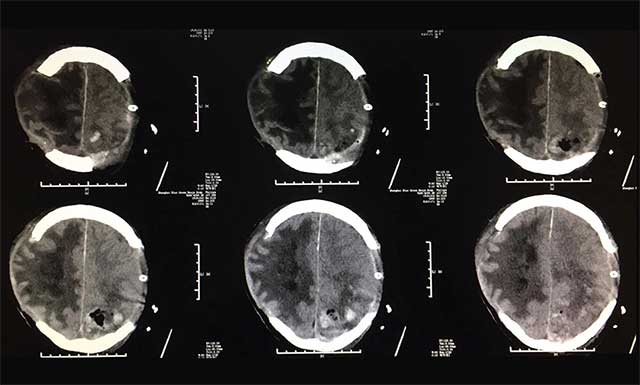

▲術(shù)后患者出血情況較前明顯好轉(zhuǎn)

術(shù)后患者影像顯示,顱內(nèi)出血較前明顯好轉(zhuǎn),看到已經(jīng)度過危險(xiǎn)期的患者,家屬感慨萬分,患者女兒更是感激的說:“這次幸好遇到藍(lán)十字如此專業(yè)負(fù)責(zé)的醫(yī)生團(tuán)隊(duì),從發(fā)現(xiàn)父親情況異常,到會(huì)診定方案,再到手術(shù)的進(jìn)行,專家爭分奪秒,救治及時(shí),我父親才得以保住了性命。”